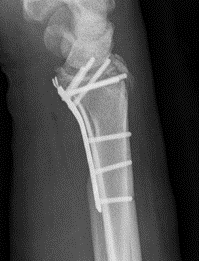

Bridge plate

- distal to index / middle metacarpal

- slide under 2nd extensor compartment (ECRL / ECRB)

- proximal to radius between brachioradialis and ECRL / ECRB

- leave for 10 - 12 weeks